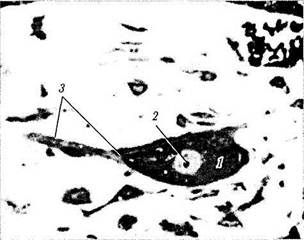

Последние исследования значительно расширили наши знания относительно особенностей иннервации сосудистой оболочки. У различных животных (крыса, кролик) и у человека артерии и артериолы сосудистой оболочки содержат большое количество нитрэргических и пептидэргических волокон, образующих густую сеть. Эти волокна приходят с лицевым нервом и проходят через крылонебный ганглий и не-миелинизированные парасимпатические ветви от ретроглазного сплетения [328, 1202]. У человека, кроме того, в строме сосудистой оболочки имеется особая сеть нитрэргических ган-глиозных клеток (положительны при выявлении НАДФ-диафоразы и нитроксидной синте-тазы), чьи нейроны связаны друг с другом и с периваскулярной сетью (рис. 3.8.59). Отмечено, что подобное сплетение определяется только у животных, имеющих фовеолу.

Ганглиозные клетки сконцентрированы в основном в височных и центральных областях сосудистой оболочки, по соседству с макуляр-ной областью. Общее количество ганглиозных клеток в сосудистой оболочке порядка 2000. Распределены они неравномерно. Наибольшее их количество обнаруживается с темпоральной

стороны и центрально. Клетки маленького диаметра (< 10 мкм) располагаются по периферии [328]. Диаметр ганглиозных клеток увеличивается с возрастом, возможно, из-за накопления в них липофусциновых гранул.

Рис. 3.8.59. Ганглиозная клетка сосудистой оболочки типичного строения, к которой подходит и контактирует нервное волокно:

/ — ганглиозная клетка; 2 —крупное ядрышко ганглиозной клетки; 3 — нервное волокно